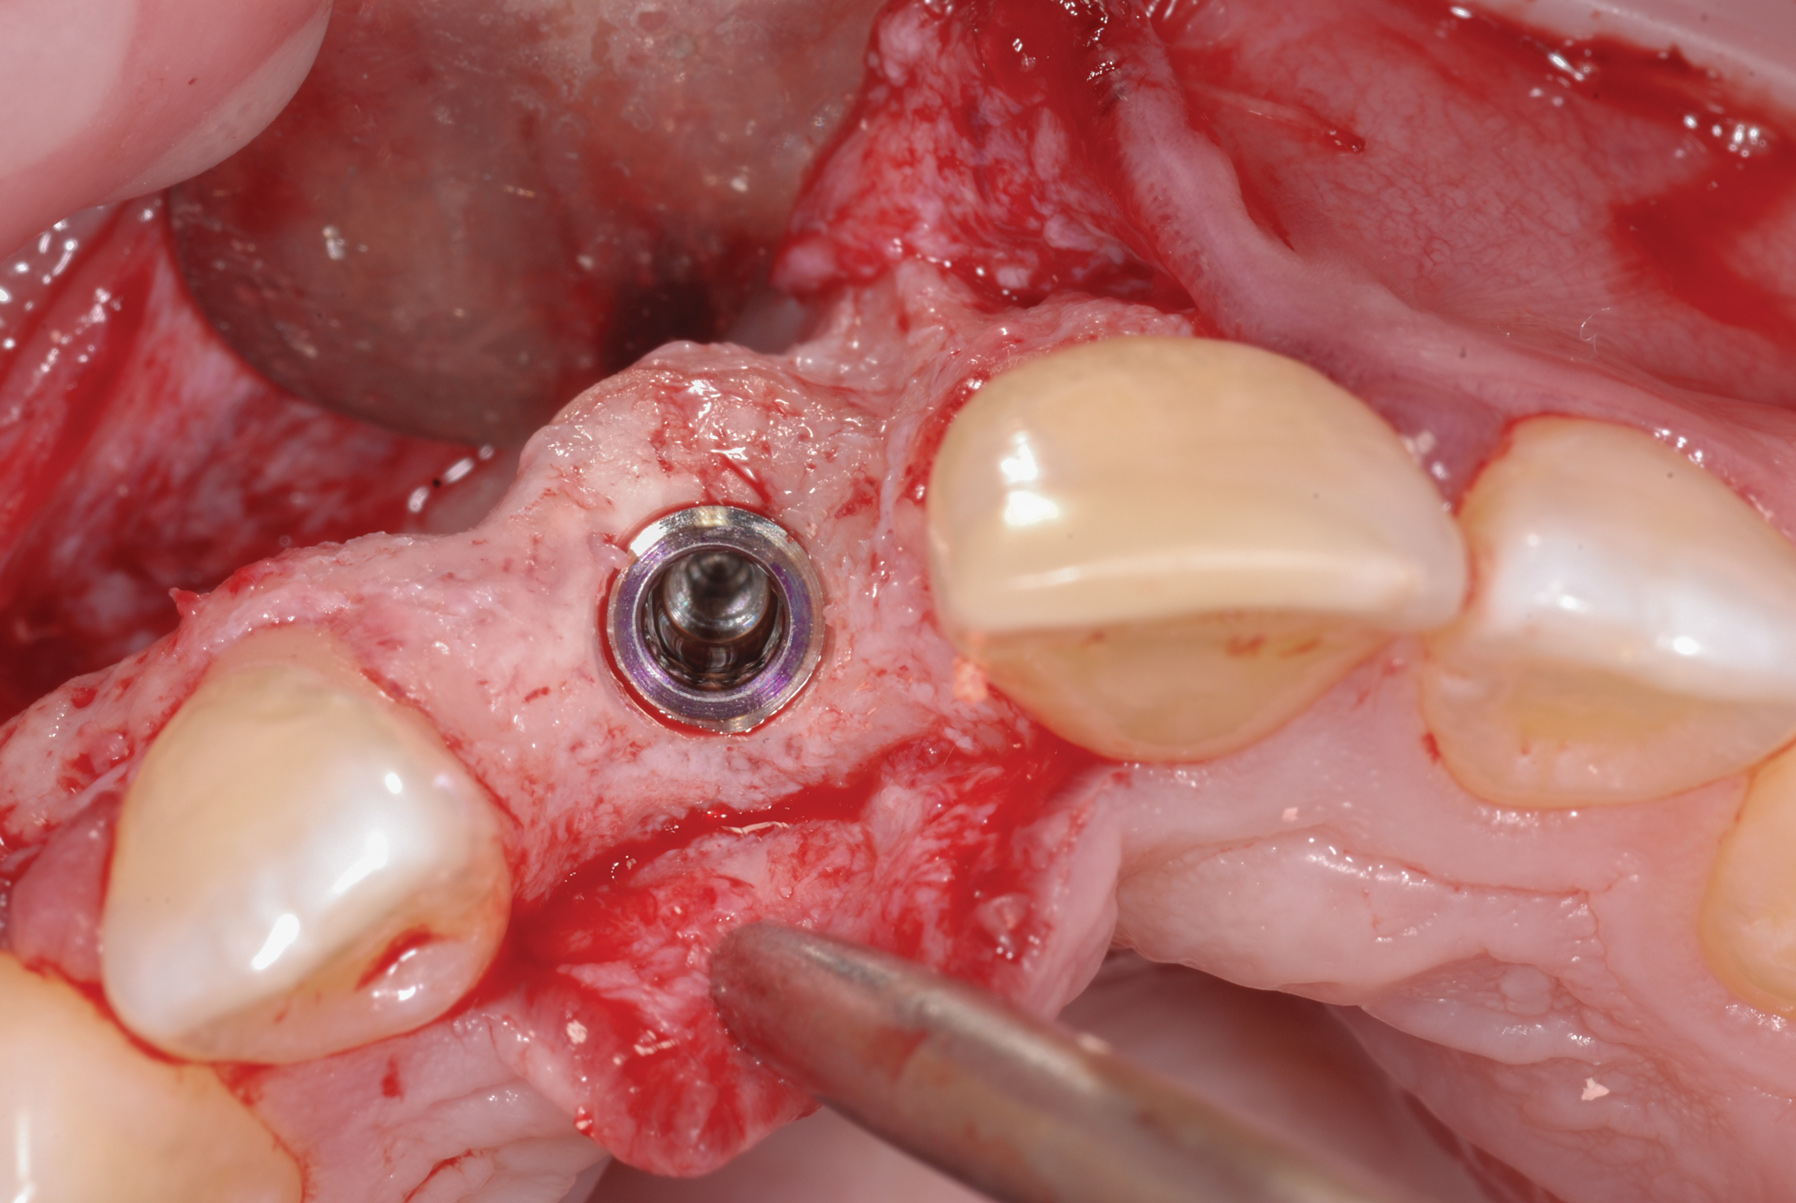

Fig 22. Bone that formed after decoronation. Note its substantial width and density.

Figure 22

At age 21, it was determined that growth was substantially com--pleted (Figure 21). At the implant surgery, a mid-crestal incision was made with adjacent sulcular incisions. The labial flap was reflected revealing a very wide ridge at the coronal aspect. The mid-labial fenestration was evident along with exposed gutta-percha. A test drill was made and a radiograph was taken, which showed that the gutta-percha was removed during the site preparation. The fixture was placed and a 2 mm healing abutment secured (Figure 22). The bone was quite dense. The labial fenestration was grafted with particulate bone and primary closure was accomplished with 6-0 nylon sutures.

The outcome of this patient's decoronation surgery was extraordinary. Figure 17 shows the deposition of bone 1 year after decoronation. Figure 22 shows the bone formed during replacement resorption of the remaining root. Both the quantity and location of bone after the procedure were exceptional. The coronal level of the replacement bone was proper for an implant fixture as was the horizontal width.